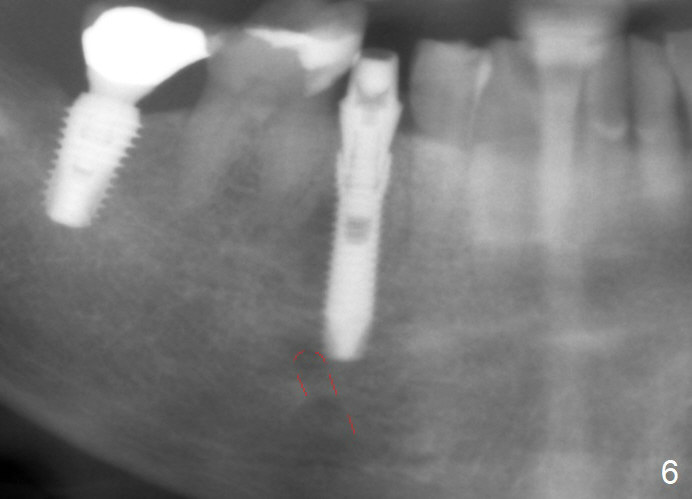

To reduce the chance to injury the buccally located loop, the osteotomy should be as lingual as possible. Initial depth is 19 mm (gingival level, Fig.3). In fact all of the three intraop PAs (Fig.3-5) do not show the Mental Loop until panoramic X-ray is taken immediately postop (Fig.6). There is no postop paresthesia. There appears no gap around the implant 3.5 months postop (Fig.7 >).